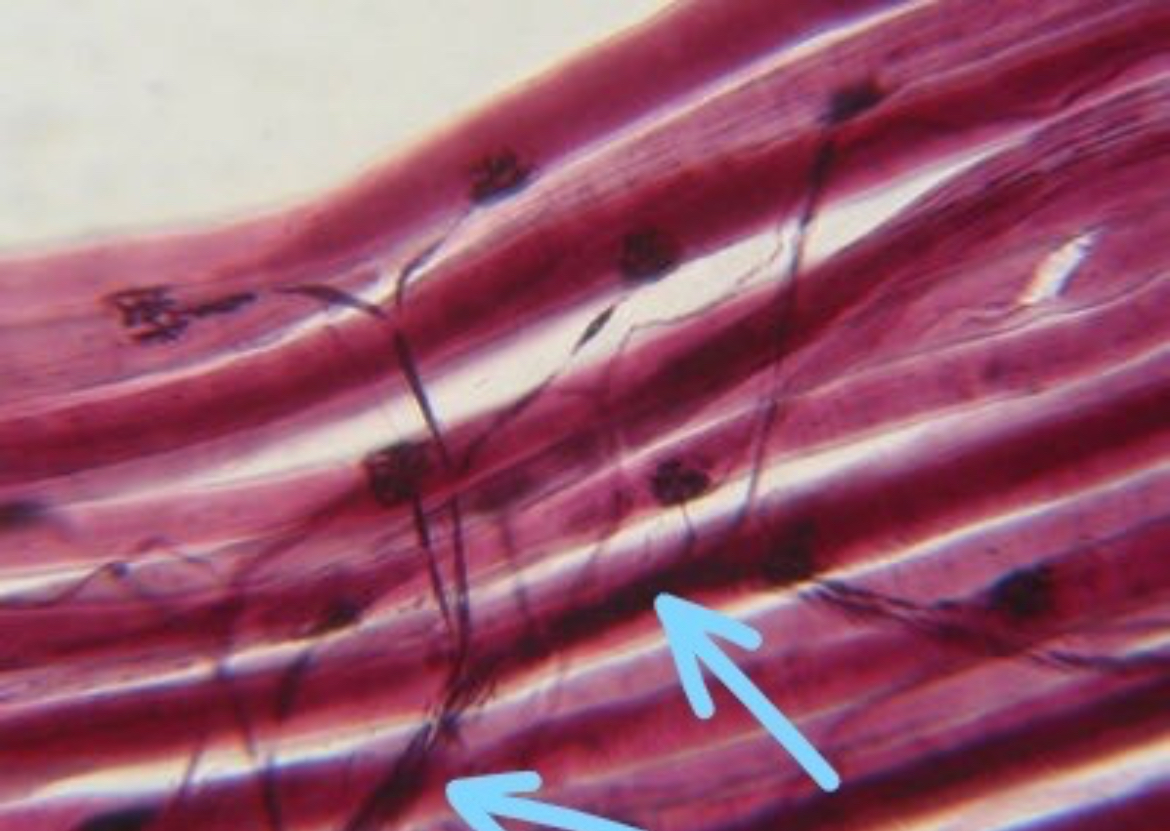

Neurofibrils

Skeletal muscles